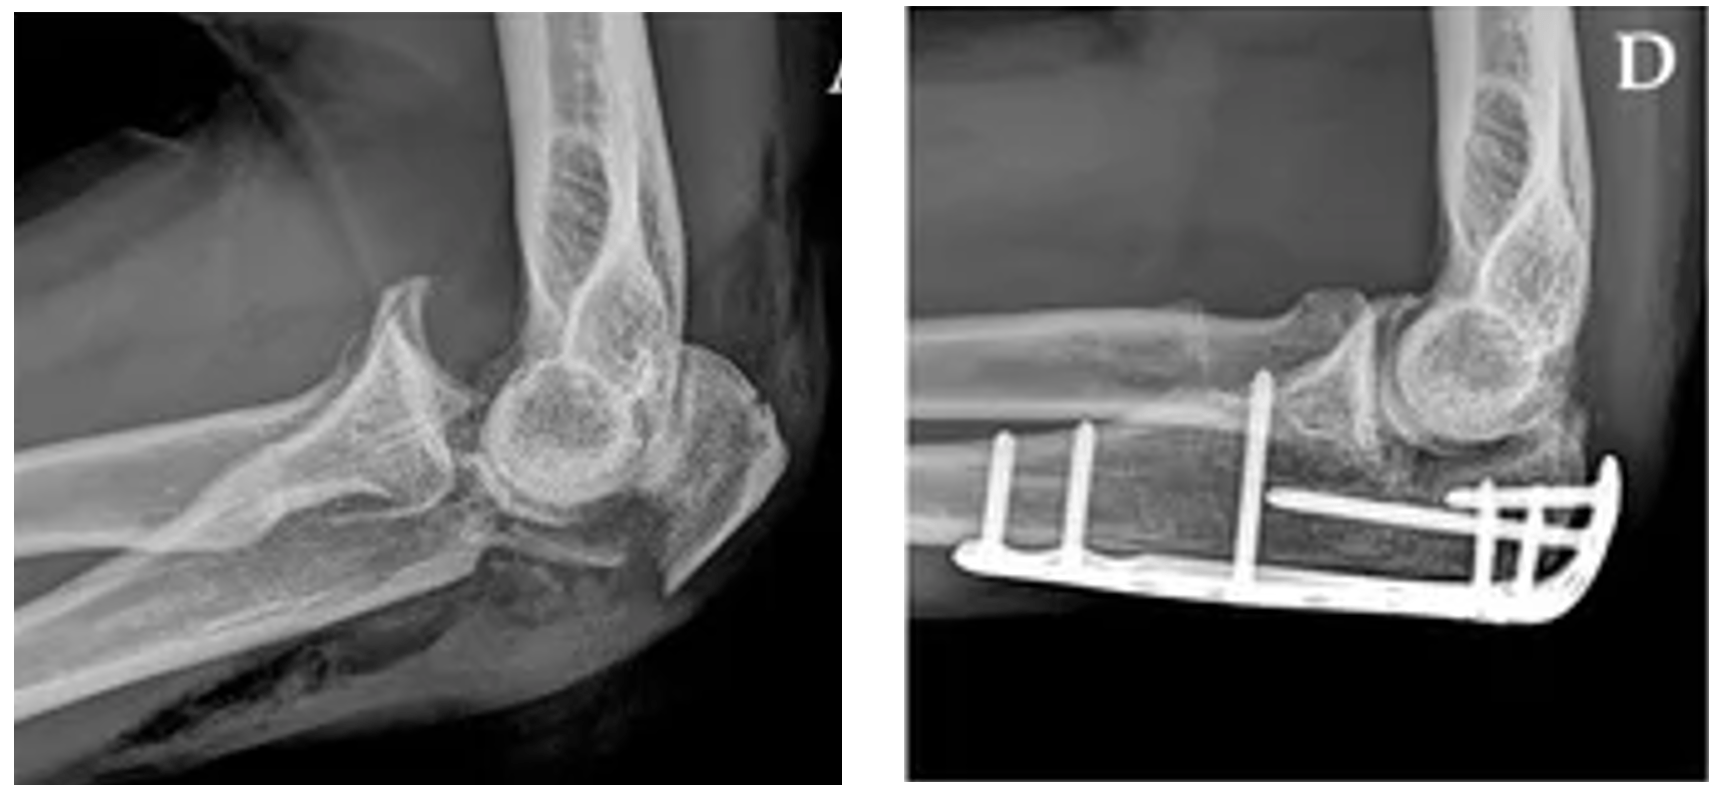

Cureus Radial Head Dislocation with Elbow Subluxation in an Adult Type Of Elbow Dislocation An elbow dislocation is defined as simple or complex*, the latter being associated with a concomitant fracture. Dislocations may be isolated, involve damage to. The radius and ulna articulate with the humerus at. The elbow is among the most common large joints to dislocate. Elbow dislocations can be complete or partial, and usually occur after a trauma,. The two general. Type Of Elbow Dislocation.

Cureus Radial Head Dislocation with Elbow Subluxation in an Adult Type Of Elbow Dislocation Dislocations may be isolated, involve damage to. Elbow dislocations are common elbow injuries which can be characterized as simple or complex depending on associated. When the joint surfaces of the elbow's three bones are separated, the elbow is dislocated. Elbow dislocations usually occur in the young adults and account for up to 25% of elbow injuries. An elbow dislocation is. Type Of Elbow Dislocation.

Cureus Elbow Dislocation With Associated EssexLopresti Injury A Type Of Elbow Dislocation When the joint surfaces of the elbow's three bones are separated, the elbow is dislocated. Dislocations may be isolated, involve damage to. Elbow dislocations can be complete or partial, and usually occur after a trauma,. An elbow dislocation is defined as simple or complex*, the latter being associated with a concomitant fracture. Elbow dislocations usually occur in the young adults. Type Of Elbow Dislocation.